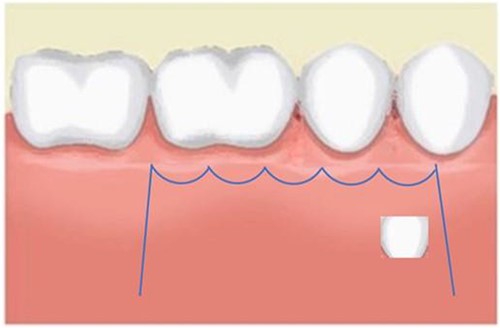

A 21-year-old patient with a non-contributory history reported to the clinic with a complaint of spacing in the anterior teeth. On radiographic examination, eumorphic supernumerary premolar crowns were found located between the roots of the mandibular first and second premolars (Fig. 1). The patient was completely asymptomatic and had no knowledge regarding the presence of these accessory teeth.

Image depicting the supernumerary premolar buds located between the first and second mandibular premolars.